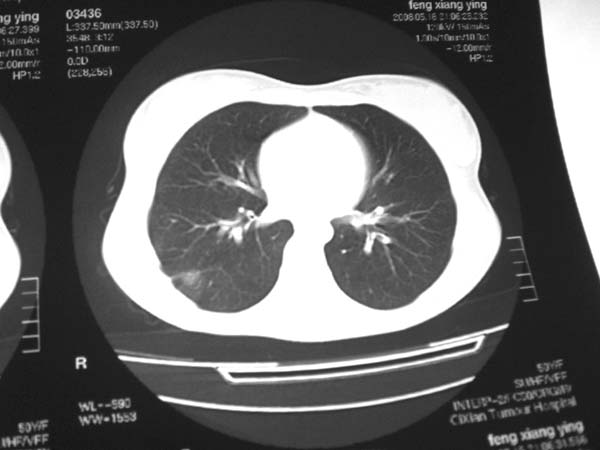

标题: CT13486:F 17Y 咳嗽 咳痰数日请会诊 [打印本页]

标题: CT13486:F 17Y 咳嗽 咳痰数日请会诊

白细胞9600不发烧

考虑右下结核球

右肺下叶结核灶

右下肺背段病灶,考虑结核与炎症鉴别,请进一步检查.

考虑结核球,建议治疗后复查

结核与肿瘤同时考虑

右下肺外基段病灶,考虑炎症,建议治疗后复查,以排外结核

考虑为:右肺下叶外基底段结核球。

结果;痰中找到结核杆菌

痰涂片已找到结核杆菌  将结果告诉大家